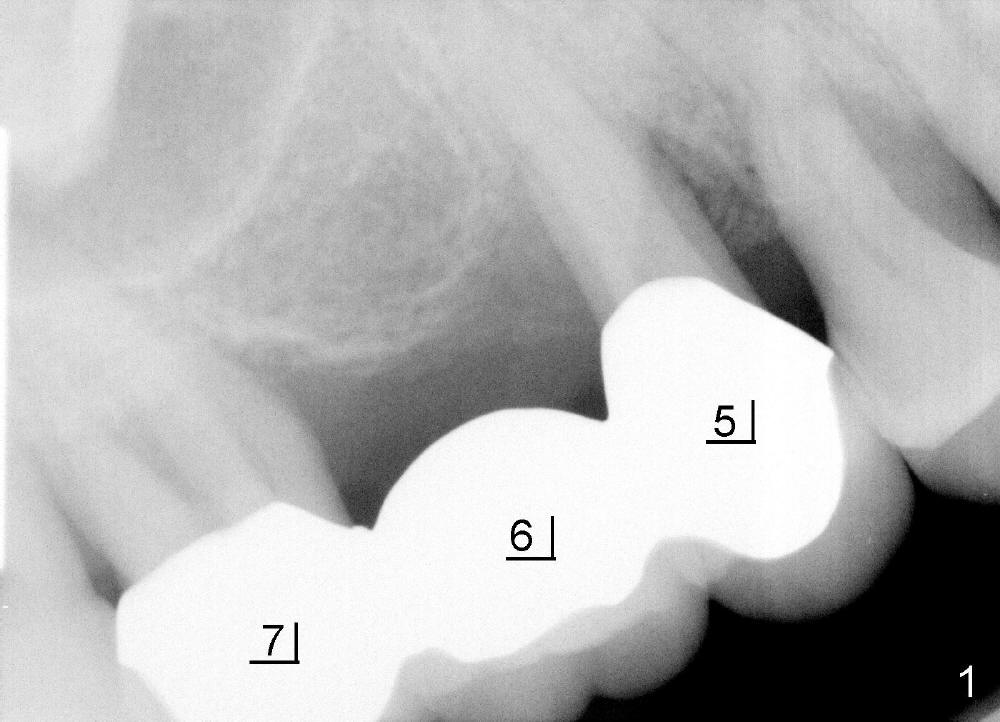

五十来岁郑先生有两个主诉:第一,左上桥松动(图二,五),要求拔除后面基牙;第二,右下六号牙处需要植牙(图三)。初步检查几张根尖片(图一至五),他是典型牙周病病人,悲观人认为不治之症,乐观人却认为这是最好植牙病例,虽然骨质吸收严重,但是剩下骨质坚硬,因为牙周病病人往往咬合力很大。充分利用剩余骨质吧。现在他口腔卫生不差。

病人要求先处理左上桥(图二,五),我们准备在五六号牙之间切断桥(图六:黑线),拔除七号牙,立刻植牙。那里骨头高度多少?是黑线,还是红线?一两天我们就会给您答复。估计在那里可以植入七或者八乘十一或者十四毫米植牙。

如果时间允许,我们可能同时在左上六号牙处植牙,骨头高度好像不乐观(图五,六),积极人在图二找骨头,估计可以植入六乘十一或者十四毫米植牙。